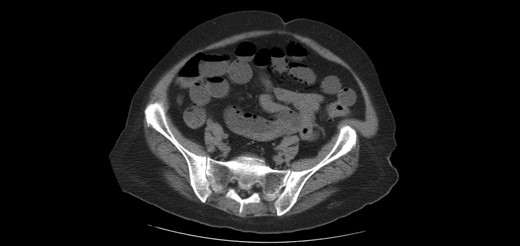

One year later, the patient was brought to the emergency department by her family for altered mental status. They reported 2 days of abnormal behavior and confusion culminating in an episode of bowel incontinence. The patient had difficulty following commands and was complaining of abdominal pain. Initial workup showed tachycardia, hypotension, leukocytosis and elevated creatinine which was treated per sepsis protocol. Her toxicology screen was positive for cocaine. Serum lactate was also elevated. CT brain without contrast showed no acute intracranial process. CT without contrast of the abdomen and pelvis, shown in Figs 3 and 4 , revealed dilated small bowel with gas in the bowel wall. Emergent damage control surgery was performed. There were no signs of gastrointestinal perforation but two segments of necrotic small bowel, 5 feet in total, were removed and the abdomen was sealed with Abthera. Two days later, her abdomen was re-explored and another 40 cm of non-viable small bowel was removed, leaving her with two small bowel anastomosis. Her abdomen was re-explored and closed after another 2 days. She was successfully weaned off the ventilator and continued to improve with supportive care. Final pathology examination revealed extensive necrosis with acute inflammation impacting the serosa at points in the small bowel.

Extensive pneumatosis of the small bowel during the second admission. Approximately 5 feet of ischemic bowel resected.